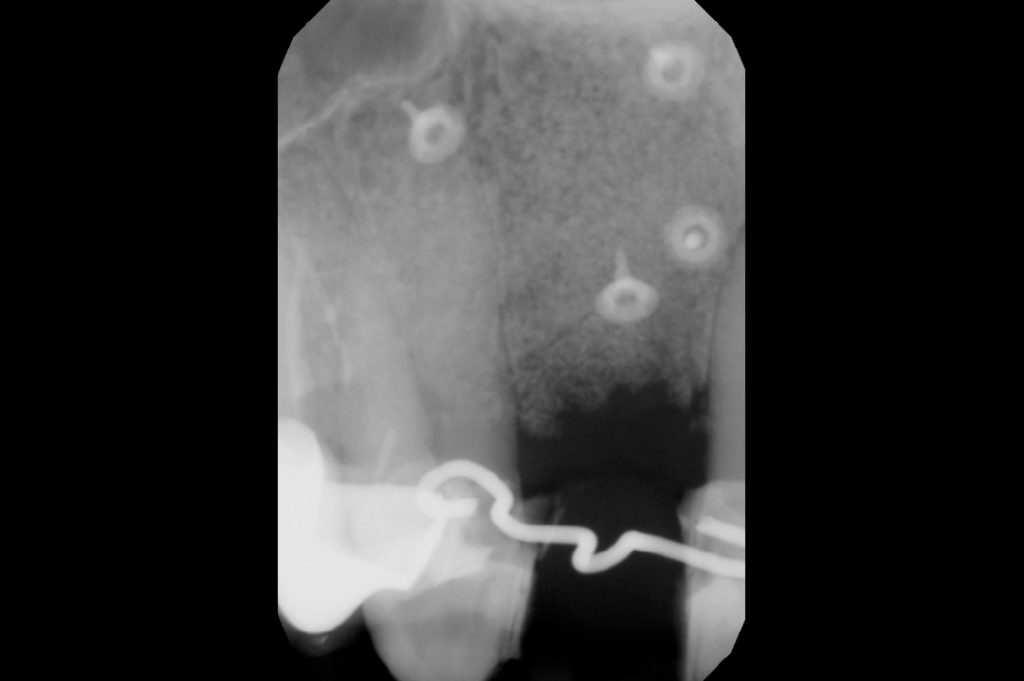

X-ray examination after six months